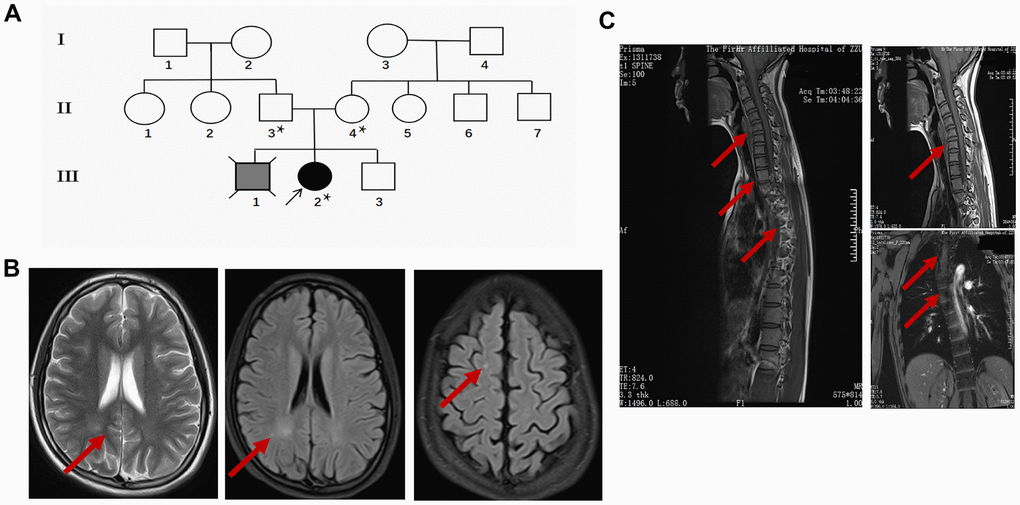

The proband (III-2) is a 15 years old female teenager with a chief complaint of “lower limb weakness and walking instability for half a month”. The parents (II-3 age 55, II-4 age 52) of the proband are healthy and had had 3 children. The first child (III-1) without clinical diagnosis or gene test died in his early 20s and suffered congenital mental retardation, and was unable to take care of himself by his death (according to the parents). The second child is the proband. In addition to the chief complaint, she also displayed slow motor response, poor coordination, difficulty in feeding after birth, and a lower intelligence compared with her peers according to her parents. The third child (III-3), a 14 years old male displayed no sign of congenital disorder and has been healthy after birth. None of the three children experienced hypoxia or possible injury at birth. The parent denied a history of drug abuse, pregnancy infection, malformation drug use during pregnancy. They also claimed no similar case in the whole family. The pedigree was made according to the parents’ narration (Figure 1A).

Figure 1. Clinical data of the proband. (A) Pedigree of the family presenting the p.Leu439Pro mutation. Circles and squares represent females and males, respectively. Clear symbols represent the healthy subject, the grey filled symbol with a cross indicates the deceased subject without clinical diagnosis or genetic examination, and the black filled symbol represents the proband. The asterisk was labeled to the individuals who received the MTHFR exon sequencing. (B) Representative brain MRI scan images in the basilar ganglia (left and middle panel) and centrum semiovale (right panel) in T2 and FLAIR sequence of the proband. Arrows indicate the white matter injury in the occipital lobe and parietal lobe. (C) Representative cervicothoracic combined MRI (left panel) slides of the proband to show the sever reverse gantry of the cervical spine (right upper panel) and scoliosis of the thoracic spine (right lower panel).

During her first visit, the proband was hospitalized for physical, biochemical, and radiology imaging examinations. The patient showed awake consciousness with normal speech and comprehension. Mildly impaired cognitive disorder in memory and calculation deficits was unveiled by the MMSE scoring (25 points, unable to do the continuity calculation) and MoCA scoring (21 points, unable to draw a clock, visual/special, naming, calculation, abstraction, delayed memory were impaired significantly) test. Physical examination showed that she displayed hypermyotonia and tendon hyperreflexia. Muscle power of the lower extremity was 4 degree for the left and 4+ degree for the right. She could not walk in a straight line and Romberg sign was positive, pathological signs including Babinski sign, Chaddock sign, Rossolimo sign were all positive (Table 1). Electromyography revealed the motor and sensory nerve conduction velocity decreased significantly in the right ulnar nerve and bilateral shin nerve, the deep sensory nerve conduction delayed in the right lower extremity by spinal somatosensory evoked potentials (SSEP). Brain and thoracic spinal cord MRI revealed white matter demyelination of both hemispheres, suggesting white matter disease (Figure 1B). Reverse gantry of the cervical spine and scoliosis of the thoracic spine, which are extremely rare signs in severe MTHFR deficiency cases, were also confirmed by the cervicothoracic combined MRI scan (Figure 1C). Biochemical tests revealed a significant increase in homocysteine and a decrease of folic acid in the blood (Table 2). While the enzyme activity of MTHFR was not tested, the gene tests, physical examination, laboratory test, and MRI scanning of the patient strongly suggested folic and homocysteine metabolism disorder, which could be due to mutations in the MTHFR gene.